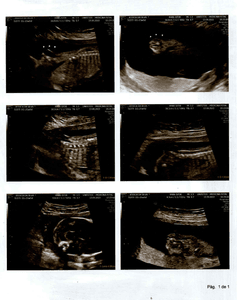

Olá amigos e amigas, eu Laidson Saturnino Souza Santos, descobri que minha filha, com idade gestacional de 21 semanas e 6 dias, foi diagnosticada com MIELOMELINGOCELE SACRAL, ESPINHA BÍFIDA OU ESPINHA ABERTA, no dia 13/09/2022, por meio de uma ultrassonografia morfológica. Ela possui uma MALFORMAÇÃO NA COLUNA. Em decorrência disto provavelmente nascerá com ANOMALIAS ESTRUTURAIS, DOENÇAS GÊNICAS, RETARDO MENTAL, CROMOSSOMOPATIAS (SINDROME DE DOWN), entre outros problemas. A única forma de tentar reverter esse problema seria uma cirurgia intrauterina, ou seja, os médicos farão uma cesárea, irão abrir o útero da mãe, chegar até meu filho, onde irão fechar a sua coluna, q está aberta. Feito isto suas chances de nascer perfeito São grandes, claro que os médicos não descartam a hipótese de haver sequelas, mas acreditamos na cura total. Se a mãe não se submeter a esse procedimento, assim q ela nascer irá pra cirurgia para fechar a coluna, mas já será tarde demais e consequentemente ficará sem andar entre outras complicações e por fim será uma menina especial pro resto da vida. Estamos aqui correndo contra o tempo, pois o prazo será até a 26ª semana, ou seja, temos 4 semanas para organizar tudo, e levantar o dinheiro. Não sabemos ao exato o quanto custa essa cirurgia, mas passa de $ 20,000 DÓLARES, aqui no Brasil. Onde moramos, Bahia, este procedimento não é realizado, só em São Paulo ou Rio de Janeiro. Então abandonaremos tudo aqui, família, amigos, ...  para tentar dar um futuro melhor para a LIZ. Estamos tentando os órgãos públicos para obtermos a cirurgia através do SUS (Sistema Único de Saúde). Mas é difícil e não temos como esperar. Então criamos uma conta para levantarmos a quantia suficiente e assim poder realizá-la. Peço que quem tiver interesse em ajudar repasse esta mensagem aos seus amigos, para juntos salvarmos a vida da minha menina.